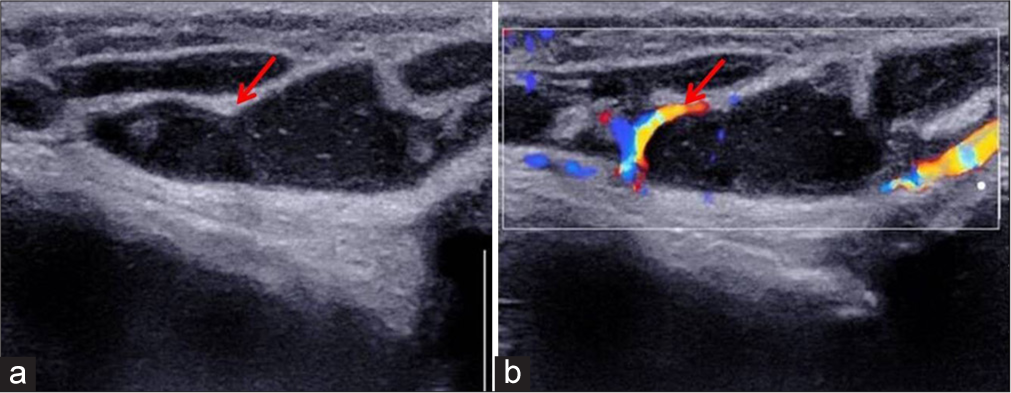

N. Karunakaran, Ganesh Rajagopal, Nancy Manodoss, S. Shanmuga Jayanthan, K. Nadanasadharam, Gowtham Ramasamy